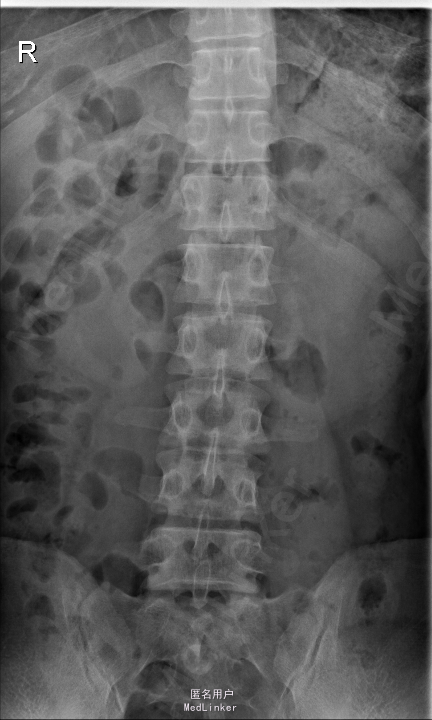

查体:腰部叩痛,腰部活动受限,左侧膝内侧、小腿外侧、内踝、足部感觉减退,右侧小腿、足背感觉减退,屈髋、伸膝、踝背伸肌肌力左侧4级,右侧4-5级,踇背伸、跖屈肌肌力左侧3-4级,右侧4级,双侧膝腱反射+,跟腱反射+,双侧巴氏征阴性,直腿抬高试验左侧40°阳性,右侧阴性。 辅助检查: X-ray:腰椎退行性变,多节段不稳 CT:腰椎间盘突出并椎管狭窄伴钙化,腰2-3,3-4,4-5,腰5骶1 MR:腰椎间盘突出并椎管狭窄,腰2-3,3-4,4-5,腰5骶1 上传受限无法全部上传,见谅

诊断:腰椎间盘突出症并椎管狭窄 处理:1、完善相关辅助检查,明确诊断,有无手术指证; 2、完善手术评估,有无手术禁忌,手术风险及并发症; 3、在全麻下行腰椎后路多节段减压椎间植骨融合内固定术 4、腰2-3,腰3-4行开窗减压,腰4-5,腰5-骶1行椎间Cage植骨融合